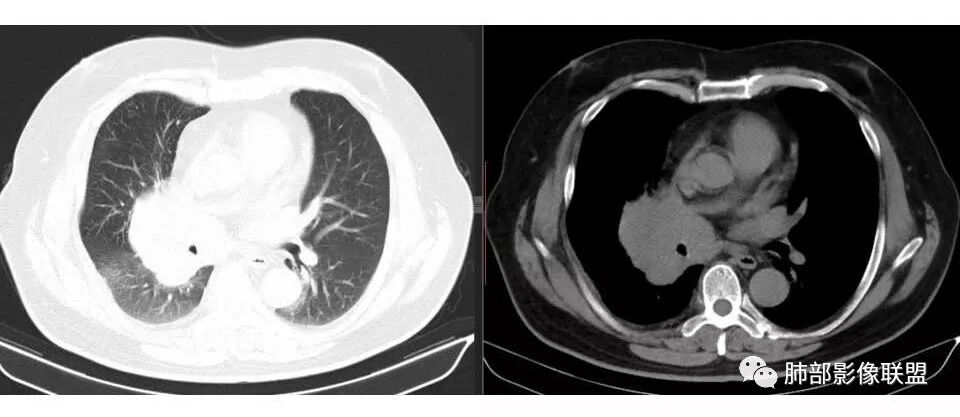

肺门及纵隔多发淋巴结。2L,4R,3区都有肿大淋巴结。

南边:有老师认为,血管前的这个应该是一个胸腺来源的。我觉得不是,为什么不符合胸腺来源呢,就看那个内乳动脉

双侧对比:右侧增粗,提示供血

但在内侧,不是外移

所以我倾向于淋巴结可能

胸腺瘤按理推压外移的多

而且胸腺癌转移不以淋巴结为主,如果淋巴结显著,按理周围侵袭性比较强,淋巴结也应该以附近为主,不应该以肺门为主,不符合引流规律。

南边: 而且肺癌,一定受叶段的局限,这一例跨越右肺门,提示多个淋巴结融合

南边: 例如这个病灶,如果是一个孤立的肿块,边界清晰,提示破坏性不强,不应该是包绕支气管,是推移到一边为主,这个表现为包绕,提示是多个病灶融合

宇宙星空: 肺门区及纵隔淋巴结肿大融合,支气管被包绕

宇宙星空: 支持南大的分析,简单总结为:冰冻纵隔,娘小崽大,右肺小结节,支持小细胞

1.右肺上叶不规则结节影,右肺门及纵隔多结节并形成巨大块影,密度均匀,沿途支气管明显狭窄。

原发灶小或隐匿,肺门纵隔淋巴结异常增大,所谓“娘小崽大”常见于肺小细胞癌!